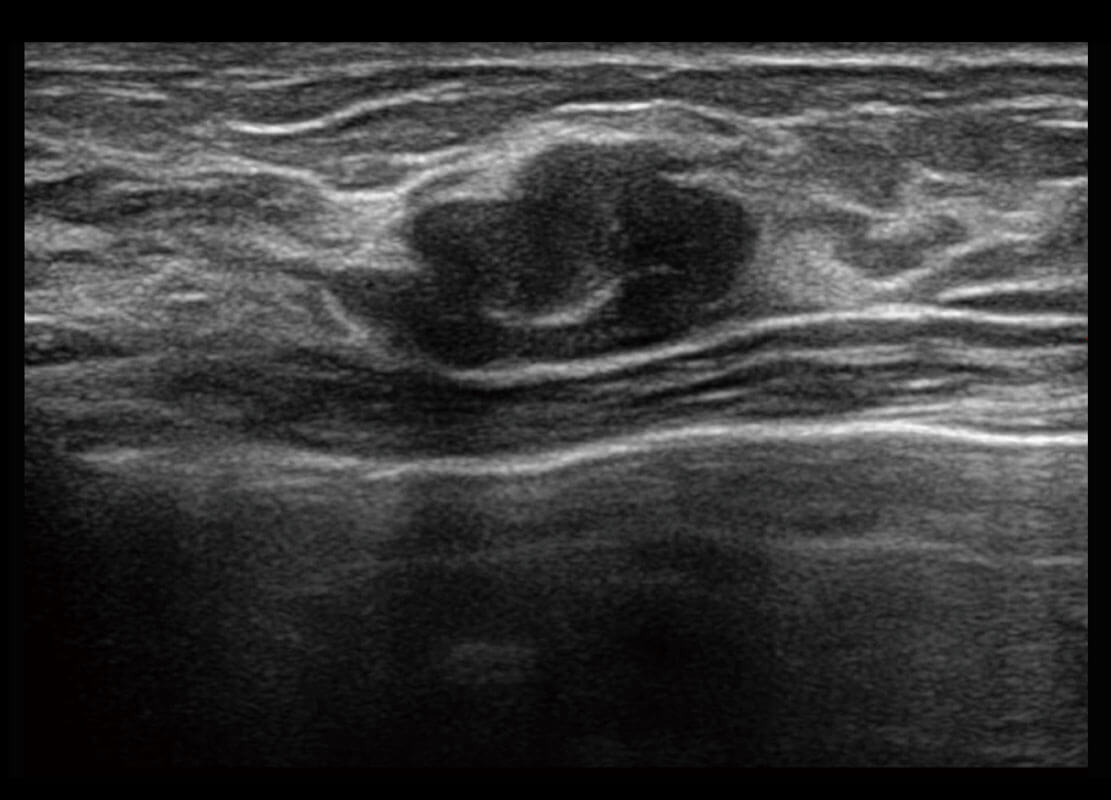

• 乳腺导管癌